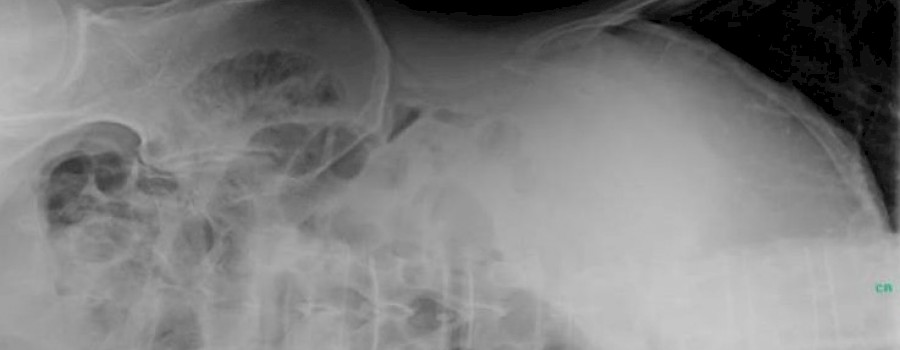

Das Coecum mobile bezeichnet eine Fixationsanomalie mit einer Fehllage des Coecums. Die normale Position des Zökums ist das Ergebnis von Rotation, mesenterialer Fixation und Deszensus durch Wachstum in der frühen Kindheit.

Was ist heute auf unserem ominösen Röntgenbild abgebildet?